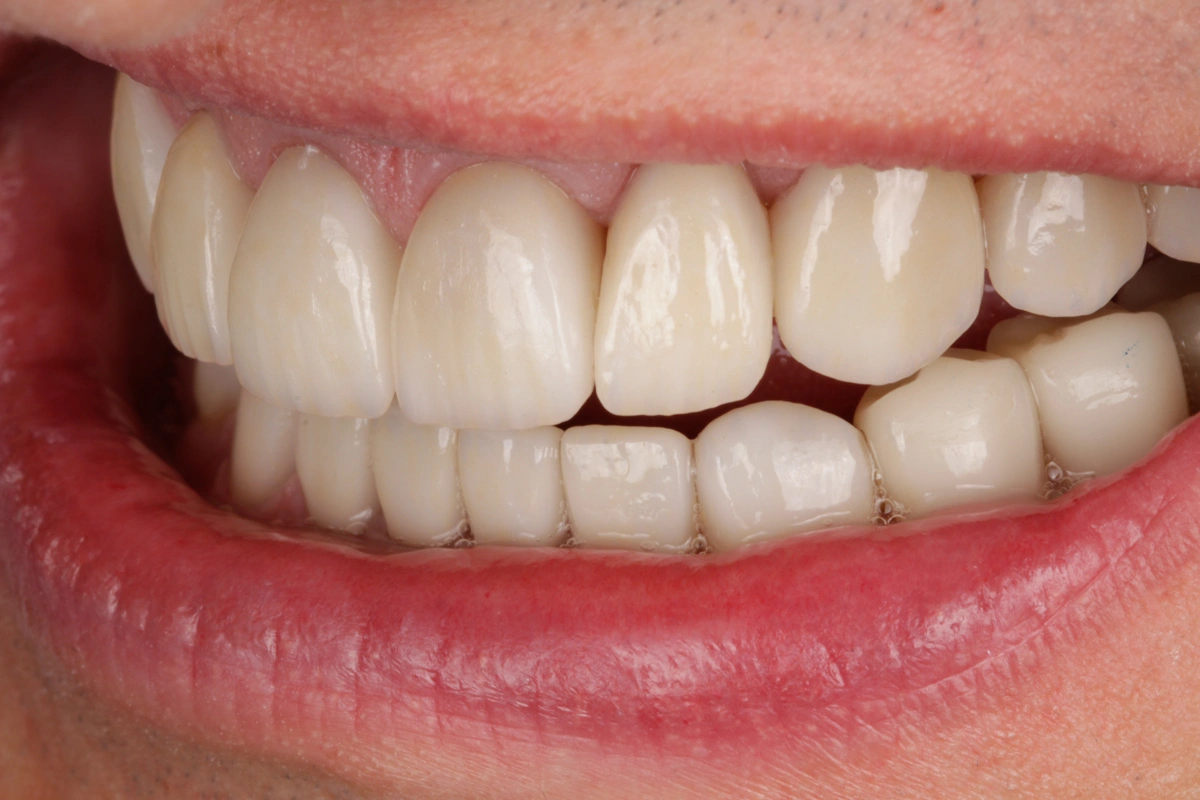

Tras realizar un estudio exhaustivo optamos por una rehabilitación completa con coronas, carillas e incrustaciones en disilicato de litio. Realizamos una prueba previa a la preparación de los dientes para establecer la longitud de los dientes definitivos.

Al finalizar el tratamiento, protegemos con una férula nocturna tipo Michigan.

Revisamos a la paciente cada 6 meses.